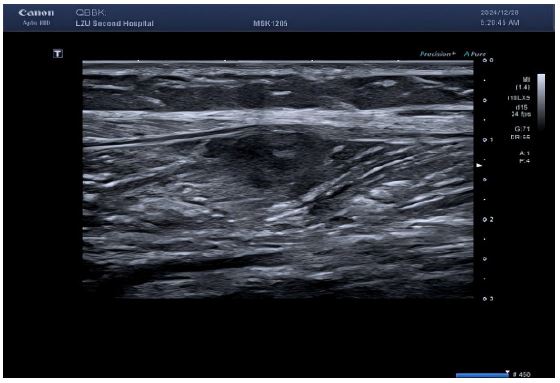

Imaging studies (Figures 1-4):

Lower limb ultrasound: Revealed multiple hypoechoic masses within the medial compartment of the right thigh and medial left calf musculature, suggestive of schwannoma; CEUS recommended.

Figure 1: Multiple echogenic areas were detected in the muscle layer of the left medial calf, all with regular morphology, clear borders, and heterogeneous internal echogenicity.